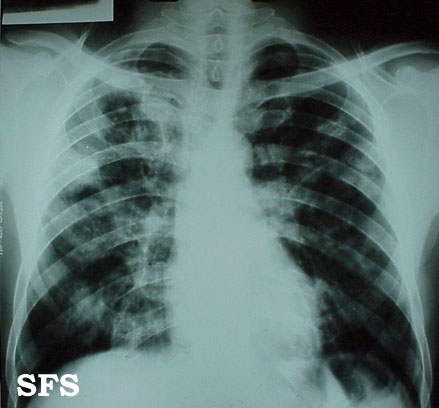

blastomycosis south american